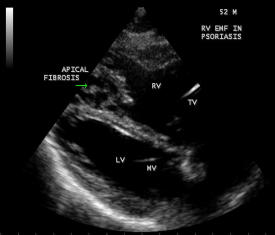

Transthoracic echocardiography revealed strong fibrous strands appearing as ‘finger like projections’ or ‘cobra-head’ appearance in the right ventricular apex due to fibrosis of muscular trabeculae, suggesting right ventricular endomyocardial fibrosis as shown in Figures 3 to 7.

Figure 5: Parasternal long axis view showing the RV (right ventricular) apical fibrosis in a 52-year old male with psoriasis

Figure 6: Dense fibrosis in RV apex in Psoriasis in a 52-year old male.

Figure 7: Thick fibrotic stands in RV apex due to fibrosis of muscular trabeculae in Psoriasis.